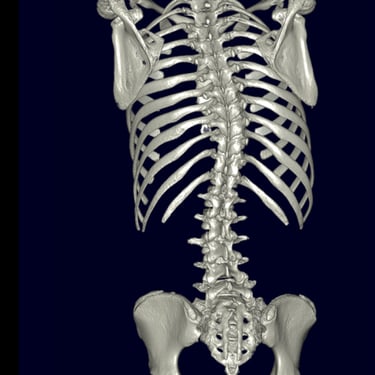

La escoliosis del adolescente idiopática del es una curvatura anormal de la columna vertebral que aparece durante el crecimiento, sin causa identificable. Su diagnóstico se realiza mediante evaluación clínica y estudios por imágenes, principalmente radiografías de columna completa, que permiten medir el ángulo de Cobb y determinar la magnitud de la desviación. En casos complejos o con sospecha de compromiso neurológico, se utiliza resonancia magnética para descartar anomalías medulares. La detección temprana es clave para definir el tratamiento adecuado —observación, uso de corsé o cirugía— y prevenir la progresión de la deformidad.